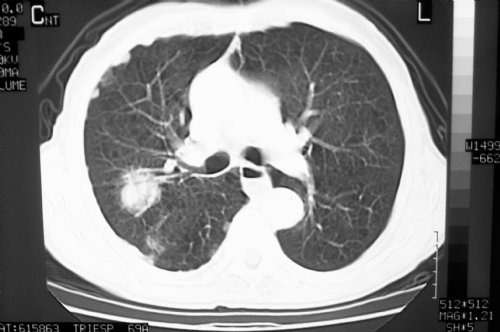

Para ver imagens de neoplasias de pulmão no PneumoImagem,

clique aqui.